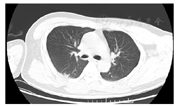

患者男,27岁,于2020年11月19日晨,被家属发现昏迷在家中(家属诉已2 d未能联系上患者),全身冰冷,四肢无活动,当时周围可见咖啡色呕吐物,室内门窗紧闭、可见烧炭的残留物,由120送入我院。查体:体温(T)36.2℃,呼吸次数(R)26次/min,血压(BP)74/35 mmHg,指氧饱和度71%。浅昏迷,巩膜及全身皮肤未见出血点,头颅无畸形,双侧瞳孔等大等圆(直径3 mm),对光反射迟钝,口唇紫绀,胸廓无畸形,双肺呼吸音粗,闻及散在湿性啰音,无胸膜摩擦音。心率(P)150次/min,律齐,未闻及杂音;全腹膨隆,腹肌稍紧张;双侧巴宾斯基(Babinski)征阴性。2020年11月19日9:00辅助检查:(1)血气分析(气管插管机械通气中、吸氧浓度FiO2:100%):酸碱度7.22、二氧化碳分压26 mmHg、氧分压154 mmHg、乳酸4.8 mmol/L、剩余碱-17.1 mmol/L、实际碳酸氢根10.6 mmol/L、COHb 16.3%。(2)血常规检查:白细胞计数19.2×109/L,红细胞计数6.43×1012/L,血红蛋白194 g/L,血细胞比容61%。(3)心肌损伤标记物检查:肌酸激酶同工酶11.2 ng/ml,肌钙蛋白1.09 ng/ml,肌红蛋白300.1 ng/ml。N-末端B型利钠肽前体15 020 pg/ml。(4)肝功能:总胆红素25.8 μmol/L,血清丙氨酸氨基转移酶137 U/L,血清天门冬氨酸氨基转移酶683 U/L,δ胆红素11.40 μmol/L。(5)凝血检查:凝血酶原时间17.0 s,国际标准化比值1.44,纤维蛋白原5.28 g/l。(6)肾功能及电解质检查:镁1.52 mmol/L,钾:3.96 mmol/L,钠147.00 mmol/L,氯108.00 mmol/L,磷2.32 mmol/L,尿素34.3 mmol/L,肌酐524.00 μmol/L,尿酸1 158 μmol/L。10:30心脏彩超检查示心脏各腔室大小正常;每搏输出量25 ml。11:00对患者头颅、胸部、腹部进行CT检查(见图1、图2):双侧基底节区片状低密度影,建议MRI检查;右下肺炎症,左下肺节段性肺不张;双肺少许纤维灶;双侧少许胸膜反应;肠梗阻。11月21日14:00下肢血管彩超:右侧股静脉、髂静脉、腘静脉管腔内异常回声,考虑漂浮血栓可能。见图3。右下肺炎症,左下肺节部他处尘肺不张,双侧少许纤维;双侧少许胸腹反应。

提示肺腔积气扩张及小液囊肠梗阻